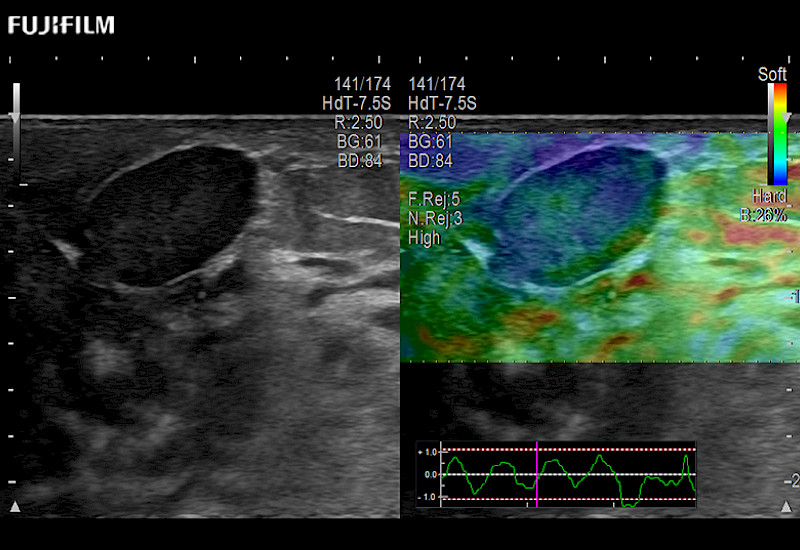

Our dedication to Surgical Oncology allows us to offer superior image quality, outstanding system reliability and intuitive use of cutting edge technology.

The ARIETTA 750 incorporates all of the proven technologies and functions that medical professionals have come to expect from Fujifilm Healthcare.

ARIETTA 750 is the definitive diagnostic ultrasound solution for any clinical setting - Private Office, Imaging Center, or Hospital. The ARIETTA platform provides the ultimate in clinical performance with its state-of-the-art features and large user-friendly display.